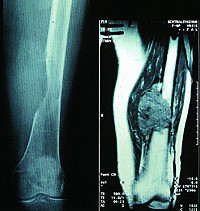

Fjernmetastaser fra nyrekreft diagnostiseres enten pga. symptomer (skjelettsmerter, cerebrale symptomer, palpabel tumor) eller ved at det tas røntgenbilde av lungene hos en asymptomatisk pasient, f.eks. som rutineundersøkelse ved kontroll etter nefrektomi. Med bakgrunn i de terapeutiske begrensninger man har ved metastaserende nyrekreft bør legen være tilbakeholdende med bevisst å lete etter fjernspredning hos en asymptomatisk pasient som tidligere er nefrektomert pga nyrekreft.

Nyrecellekarsinom er bare moderat til lite strålefølsom. Ved lokale problemer fra metastaser til skjelett, hjerne og bløtdeler bør likevel radioterapi vurderes som tumorreduktiv palliativ behandling, særlig i de tilfellene hvor palliativ kirurgi ikke kan gjennomføres. Den optimale totaldosen og det gunstigste fraksjoneringsmønster er ukjent. Vanligvis gis det 3 – 3,5 Gy ⋅ 10 over to uker. Subjektiv respons oppnås hos 70 % av pasientene og objektiv partiell respons hos 50 % (3). Postoperativ strålebehandling etter metastasekirurgi bør diskuteres for å minske risikoen for fornyet tumorvekst i pasientens levetid.